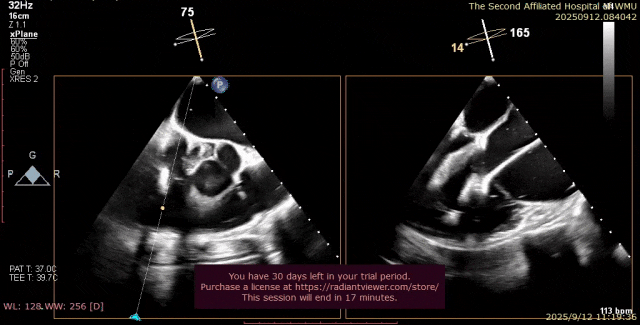

心脏超声示左室增大,二尖瓣2、3区脱垂伴重度反流(腱索断裂),Carpentier分型Ⅱ型,典型Barlow综合征表现;二尖瓣开放面积5.0cm²,3区瓣环内径31mm,前叶长22mm、后叶17mm,前叶收缩期关闭瓣体部分呈拱形突向左房腔,瓣膜游离缘对合欠佳,可见腱索断裂,长度9mm;2区瓣环内径32mm,前叶长22mm、后叶10mm,前后叶均可脱垂;三尖瓣重度反流。CDFI示瓣口重度偏心性反流,反流束沿主动脉后壁走行,肺静脉收缩期可见反向频谱。

术前超声